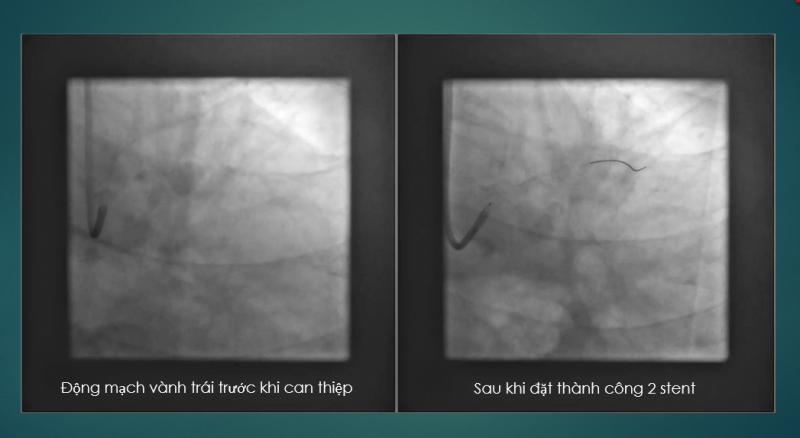

Ths.Bs Cao Việt Cường (Trưởng khoa Tim mạch can thiệp) cho biết: Việp áp dụng kỹ thuật Rotablator để xử trí các mảng xơ vữa vôi hóa, đã giúp kíp can thiệp dễ dàng đặt 02 stent vào lòng động mạch bị hẹp khít giúp khai thông dòng chảy ở động mạch vành trái. Sau can thiệp người bệnh hồi phục tốt đặc biệt không còn triệu chứng đau ngực.